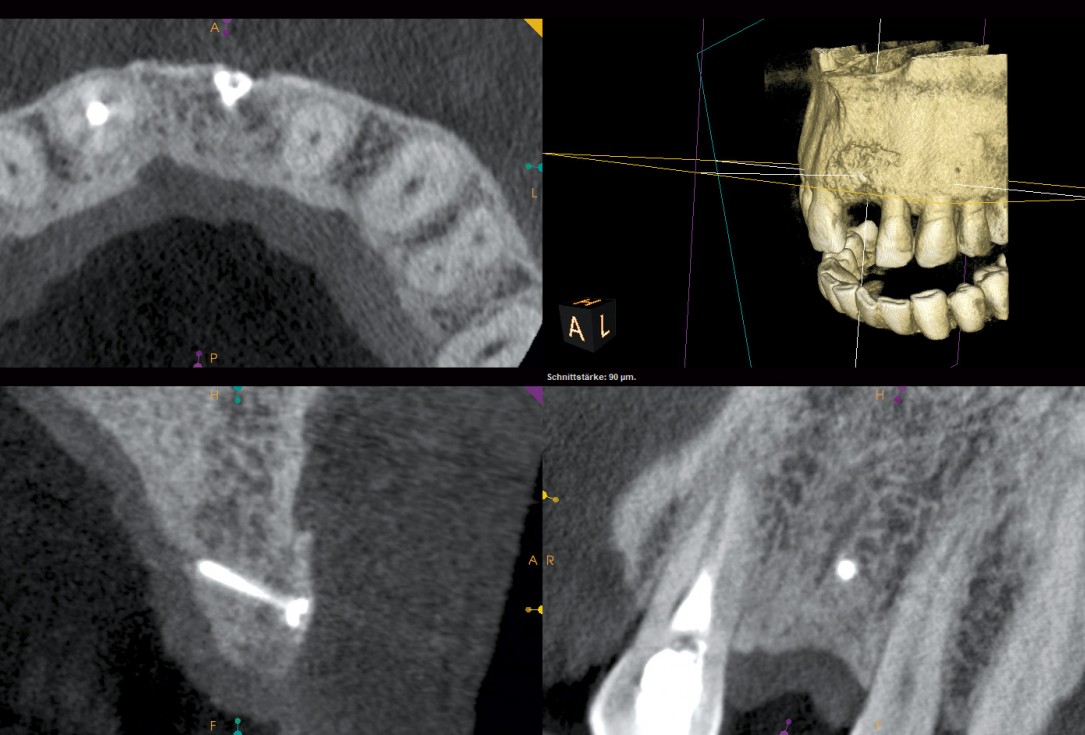

01/18 - Initial CBCT scan - Fracture of left maxillary incisor and loss of buccal wall

Block augmentation with maxgraft® and cerabone® – PD Dr. Dr. F. Kloss